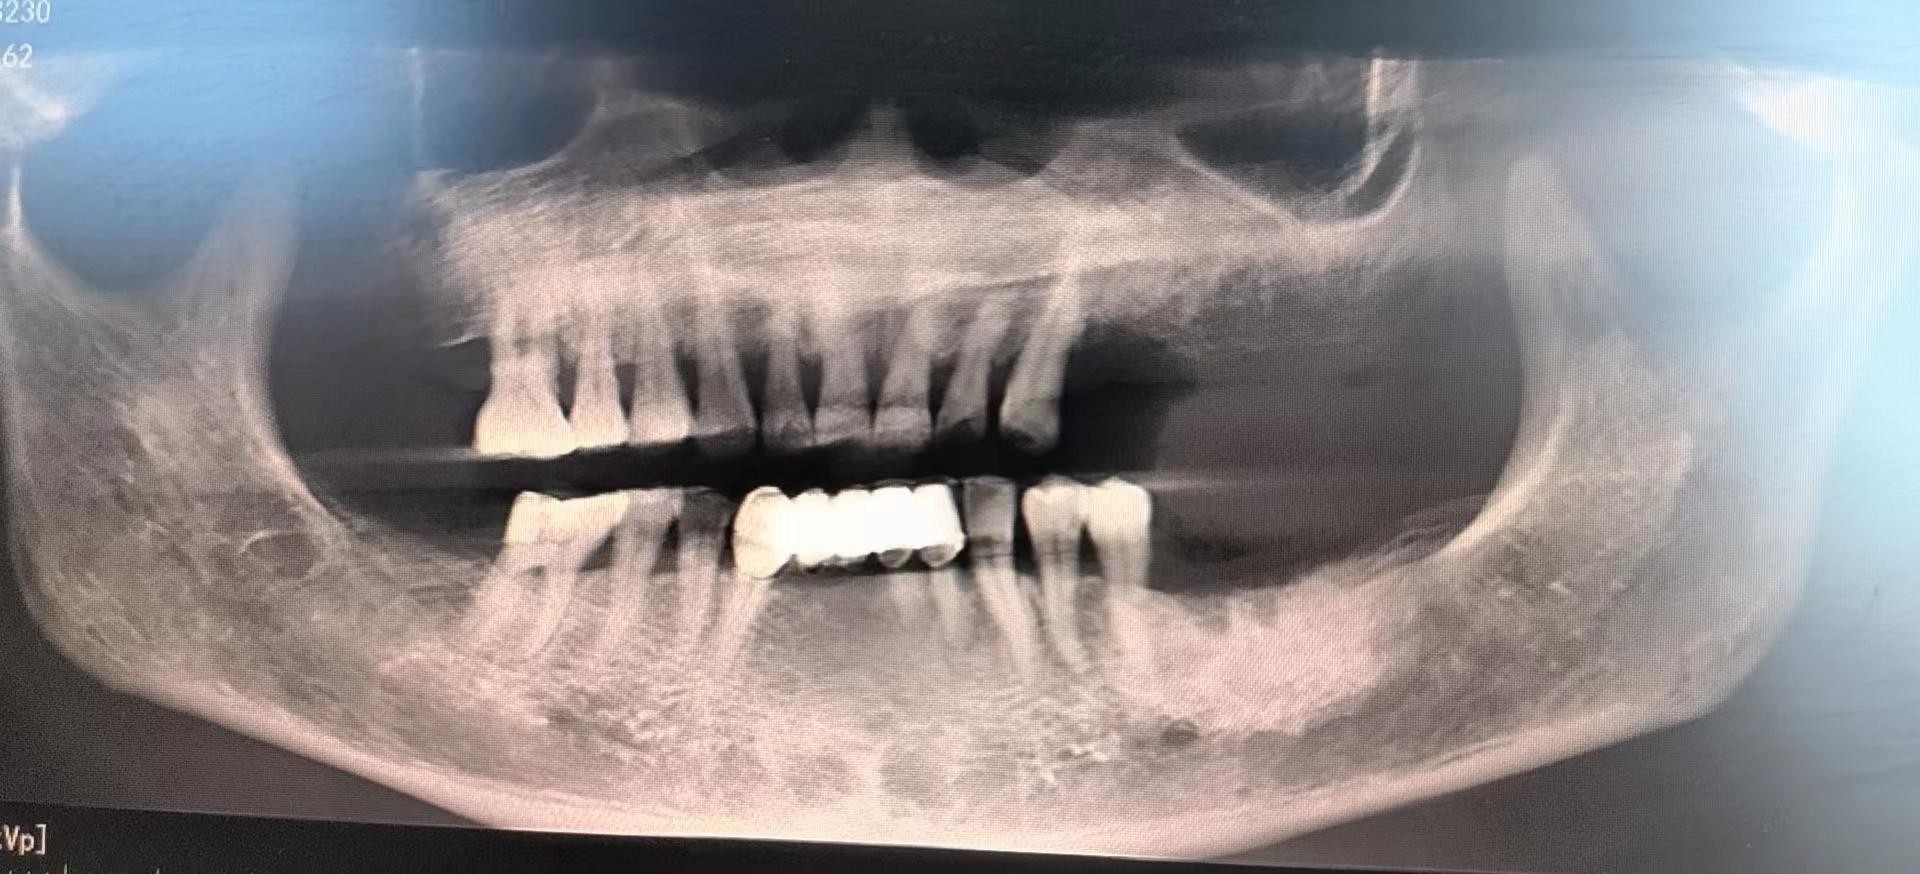

醫(yī)生檢查后,安排患者拍攝口腔CBCT,確定牙槽骨情況,并制定種植計(jì)劃,查血常規(guī),凝血功能,血壓,免疫檢查等。

為了避免患者在炎熱的夏季來(lái)回奔波,口腔科高艾玲主任團(tuán)隊(duì)決定為病人一次性種植三顆缺失的牙齒。辛璐醫(yī)生告訴患者,將通過(guò)牙科手術(shù)將人工牙根植入牙槽骨內(nèi),然后將牙齦縫合,大約10天左右拆線,之后等待骨愈合后進(jìn)行二期手術(shù)。

通過(guò)術(shù)中收集自體骨的形式,滿足了患者不能植人工骨的需求,以有利于患者的方式順利完成手術(shù)。